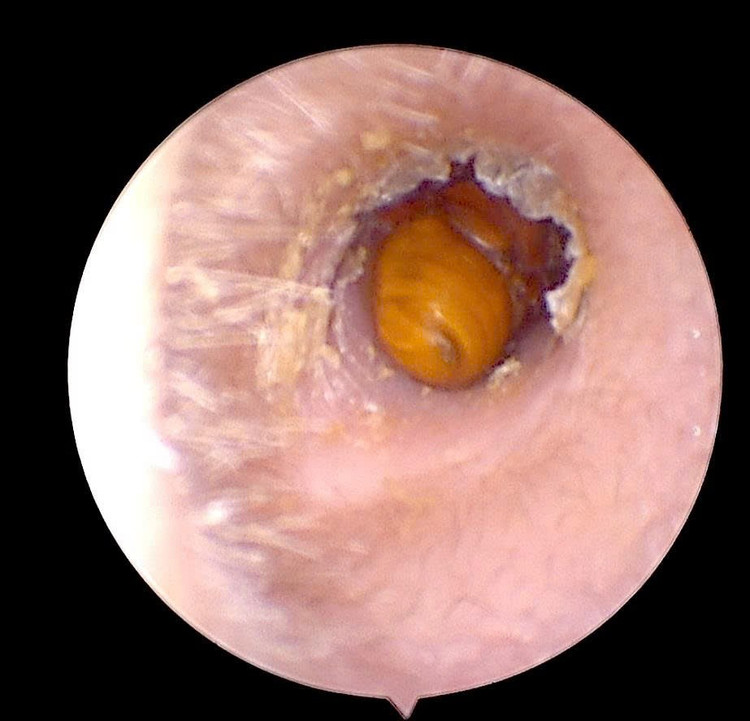

Qua thăm khám và nội soi tai, bác sĩ phát hiện một dị vật là côn trùng còn nguyên vẹn, kích thước khoảng 0,5 cm, nằm sâu trong ống tai phải. Côn trùng di chuyển trong tai khiến màng nhĩ tổn thương, sưng nề và xung huyết, gây cảm giác đau nhói và ù tai liên tục.

Côn trùng chui trong ống tai gây tổn thương - Ảnh BVCC

Ngay sau khi xác định vị trí dị vật, bác sĩ đã tiến hành lấy dị vật dưới nội soi với thao tác cẩn trọng, an toàn, tránh làm tổn thương thêm màng nhĩ.

Quá trình xử trí diễn ra nhanh chóng, dị vật được lấy ra hoàn toàn, tai được làm sạch và kiểm tra lại tổn thương. Hiện bệnh nhân đã ổn định, giảm đau và nghe rõ hơn, được hướng dẫn chăm sóc, theo dõi phục hồi tại nhà.